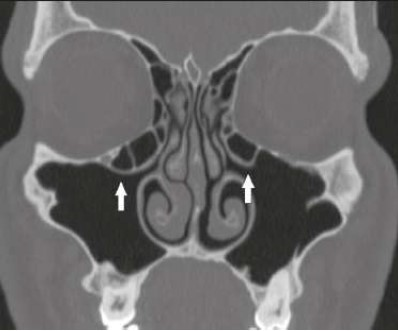

O avanço nos exames de imagem permitiu uma ampliação do conhecimento anatômico e melhor planejamento para tratamento dos pacientes. A introdução da cirurgia endoscópica nasossinusal funcional na década de 1980 trouxe uma mudança drástica na abordagem dos pacientes com rinossinusite recorrente ou refratária, aliviando os sintomas e melhorando a qualidade de vida. A imagem mostra um corte coronal de uma tomografia computadorizada, sendo possível observar na ponta das setas:

Na figura acima, de uma tomografia computadorizada dos seios paranasais, é possível observar na ponta da seta: